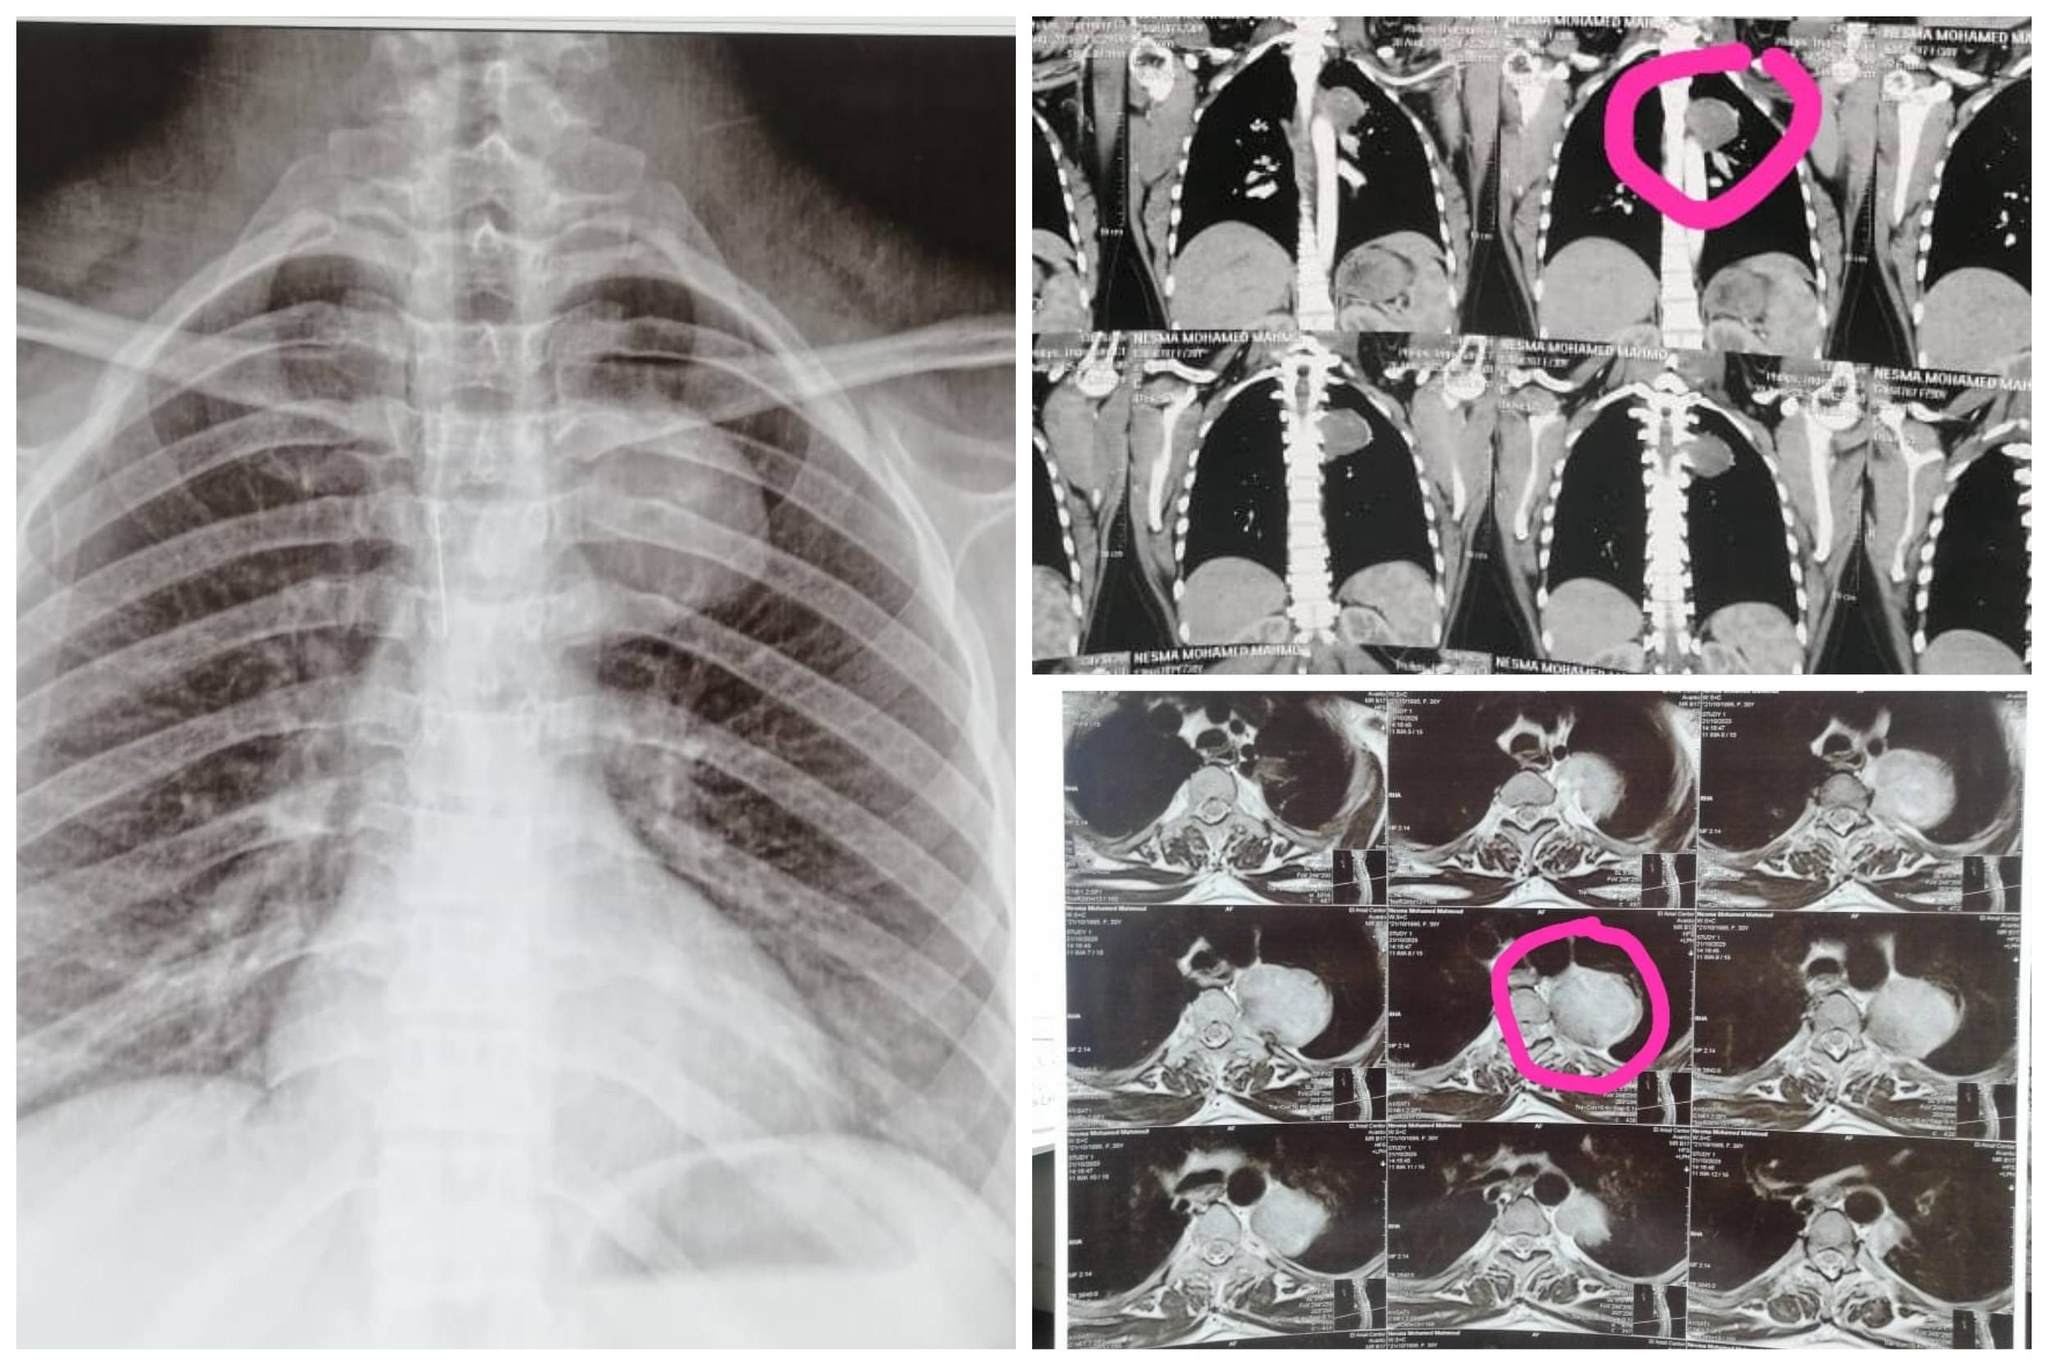

كان مستشفى الأمراض العصبية والنفسية وجراحة المخ والأعصاب برئاسة الأستاذ الدكتور طارق راجح، قد استقبل سيدة تبلغ من العمر ٢٥ عاما، حامل في شهرها الأول، وتعاني من إلتهابات رئوية متكررة، وبعد فحصها من قبل فريق من المتخصصين #بقسم_الأمراض_الصدرية، تحت إشراف الأستاذة الدكتورة صفاء وافي، وضم الدكتورة صفاء عبد الجيد، استشاري الأمراض الصدرية، والطبيب يوسف ثروت، طبيب مقيم بالقسم، بمشاركة الطبيبة شروق كيلاني، مدرس مساعد بقسم طب القلب، أظهرت الأشعات وجود ورم معقد بالعمود الفقري ممتد إلى الرئة.

تشكل على الفور فريق طبي من #قسم_جراحة_المخ_والأعصاب تحت إشراف الأستاذ الدكتور محمد السيد رئيس القسم وضم كل من، الدكتور علي أحمد عبد العليم، مدرس بالقسم، والطبيب محمد الغرياني، مدرس مساعد بالقسم، وفريق طبي من #قسم_جراحة_القلب_والصدر تحت إشراف الأستاذ الدكتور محمد عياد، رئيس القسم ومدير مستشفى القلب، وضم كل من، الأستاذ الدكتور حسين الخياط، أستاذ جراحة القلب والصدر، والطبيب محمد ربيع، مدرس مساعد بالقسم، والطبيب أحمد يونس، طبيب مقيم بالقسم، يعاونهم فريق طبي من #قسم_التخدير جاء تحت إشراف الأستاذة الدكتورة هالة سعد، وضم، الدكتور هيثم محمد، مدرس بالقسم، وقاموا بإجراء العملية باستخدام تقنية التدخل المحدود، لتقليل الضرر، عن طريق فتحة صغيرة بالظهر (حوالي ٣ سم)، تم من خلالها التدخل بـالميكروسكوب الجراحي عالي الدقة لاستئصال الجزء الشوكي من الورم مع الحفاظ التام على الأعصاب المحيطة، وفتحة أخرى بالصدر ٣ سم تقريبا، تم استخدام منظار الصدر الجراحي للوصول إلى الجزء الممتد للرئة واستئصاله، مع الحفاظ على وظائف الرئة.